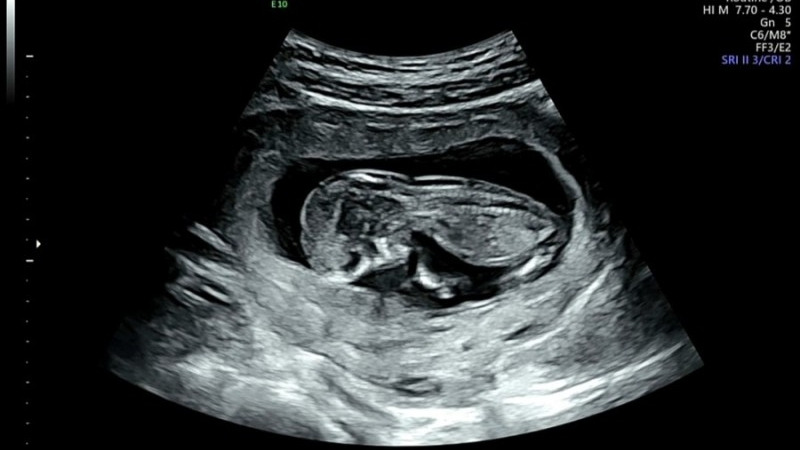

덕순이는 지난주에 1차 검사를 무사히 통과했다.

두개골 안에 뇌가 잘 자리 잡고 크는 것도 보았고,

척추가 자라 움직이는 것도 보았다.

그리고 모두가 두려워하는 목 투명대 검사도 1.45mm로 무사히 통과했다.

목 투명대 검사는 3mm가 넘으면 고위험군 판정을 받을 수 있기 때문이다.

너무 다행스러웠고, 잘 자라준 덕순이에게 너무 고마웠다.